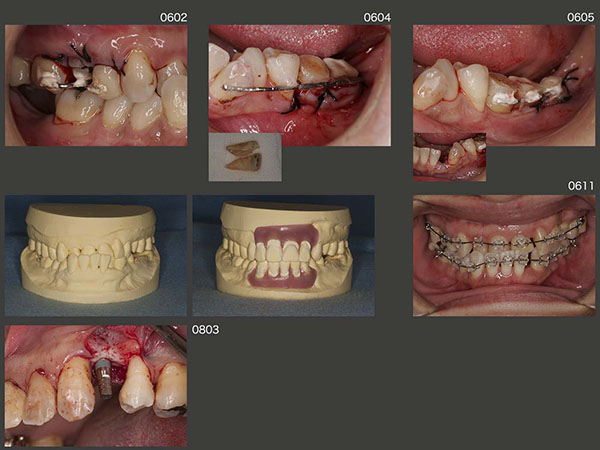

主訴の左上1を仮に修復し,一通りの基本治療を行った後の2006年2月,右上8の矮小歯を右上5部に移植した.さらに4月に,対合歯のない右上7を頰舌側に分割し,それぞれを左下に移植するという比較的難易度が高い移植を行った.続いて5月に,歯科矯正するに伴って必要がなくなる,舌側転位している左下2を左下の一番奥に移植した.これで左下は3本移植されたことになる.

左下の移植歯も固定源に利用し,06年11月に,下顎の歯科矯正に取りかかった.なお上顎は,少し前の8月から歯科矯正を開始している.08年3月,左上4部に,直径3mmの細いインプラントを植立した.ここは暫く人工歯を接着していたが,時々外れるので仕方なくインプラントを用いた経緯がある.両側がバージントゥースであり,しかも審美領域であることから今でも,補綴設計に悩む所である.